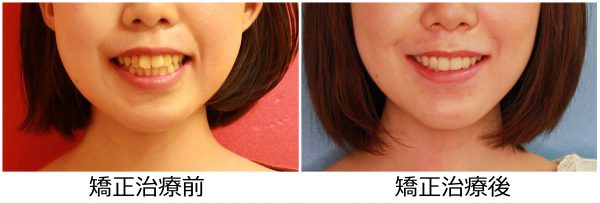

13歳 女性 「 八重歯 出っ歯を 治したい」 ( 上下顎叢生)

13歳の女性 です。

「八重歯と出っ歯をなんとかして欲しい」との事で来院されました。

前歯の段差が激しく、”八重歯”の状態です。

前歯が前に傾斜しているため

”出っ歯”も気になるとの事です。

叢生を伴う 上顎前突症 です

矯正治療のために 上下左右の 抜歯を行い

段差を解消し、前歯を後方に移動させました。

2018年の7月7日にスタートして 2019年の11月2日に 終 了しました。

治療期間は 16か月でした。

歯ならびは綺麗に整い ”八重歯” と ”出っ歯” 感は解消されました。

口元がスッキリ しました。

口もとの 印象が 大きく変わり お母さんが一番喜ばれていました。

素敵な笑顔になりました! (#^.^#)

まだ 15歳 (^◇^)! この笑顔で

これから 素敵な青春をお過ごしください!

13歳 女性 叢生を伴う 上顎前突症 治療期間16か月 唇側矯正装置(ホワイトワイヤー)を使用した上下顎第一小臼歯抜歯治療 参考治療費 約65万円 (精密検査から終了まで) 矯正治療に伴う副作用の歯肉退縮、知覚過敏、失活、歯根吸収などは認められませんでした。